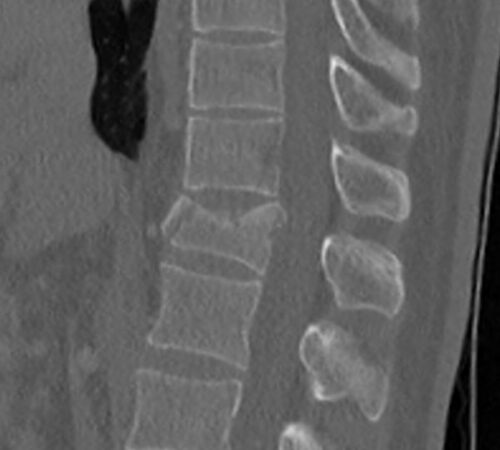

CT

CT (počítačová tomografie) je skvělé na zobrazení kostí a přesné určení, kde je zlomenina a o jaký typ se jedná.

U pacientů s více zraněními (polytrauma) se RTG často přeskakuje a rovnou se dělá CT (celé páteře, protože je to rychlejší a detailnější. Pokud je poranění méně závažné, CT se zaměřuje jen na postiženou oblast, přičemž se prohlédne alespoň tři obratle nad a pod místem zranění.